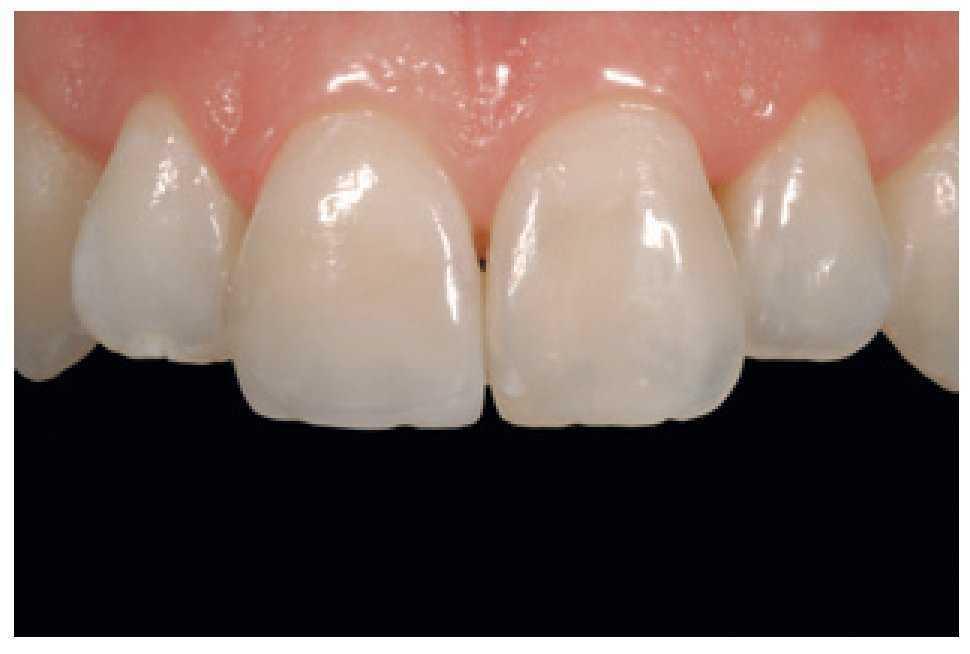

Figura 49 Vista de las restauraciones y los elementos rehidratados después de 72 horas.

Figura 50 Buena integración estética de las restauraciones y salud de los tejidos periodontales 30 días después del tratamiento.